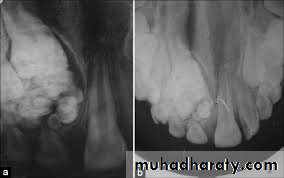

1- odantomacalcified odontomas, (simple enamel pearls and cementomas) usually consist of one or more kinds of tooth elements, enamel pearls consist of enamel. odontomas consist of dentine, cementomas are consist of cementum, odontomas may be composite by manifesting two or more tooth tissue elements. These simple tooth tumors arise from some aberration of the tooth germ early in life.

Surgical intervention is instituted at an early age to prevent derangement of the permanent dentition. In later years multiple cementomas and ossifying fibroma appear frequently near the roots of

teeth. The teeth remain vital with absence of subjective symptoms